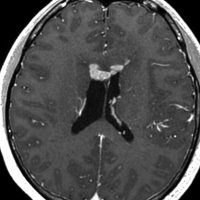

ガドリニウム増強では,前頭葉腫瘍というより,側脳室壁にベトベトくっついているような腫瘍です。germinoma特有のsubependymal infiltration像を示します。

生検後2ヶ月,セカンドオピニオンのために受診された時の画像です。腫瘍が縮小傾向にあります。入院中に行われた何度かのCT被曝の影響で,germinomaの退縮が生じたのだと判断しました。